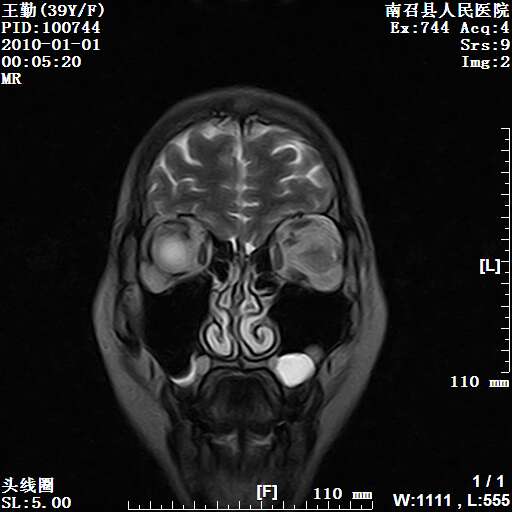

以下是引用随光逐影在2010-1-22 9:03:00的发言:[br]考虑左侧中颅窝(蝶骨翼区)脑膜瘤侵犯蝶骨翼并突入左侧眼眶。

以下是引用水过无痕在2010-1-22 14:55:00的发言:[br]一、定位:颅外占位;二、定性:恶性可能性大;三、组织来源:来源于左侧眼外直肌或其他部位;考虑为:横纹肌肉瘤>转移瘤>脑膜瘤.